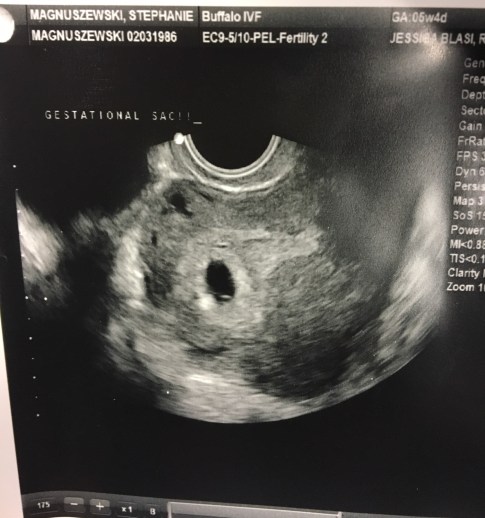

Best moment this week: We had our first sonogram today! They told me everything looks great and they saw everything they would expect to see at this point in the pregnancy. We had a clear gestational sac with a nice thick cushion around it and it appeared to be in the right place. The measurements of it were perfect too. We’ll be back for another sono in 2 weeks at which point we should be able to see the itty bitty baby and maybe even a heart beat at that point.

Here is baby’s FIRST photo! Doesn’t look like much, but in a few weeks we’ll see an actually baby in there!